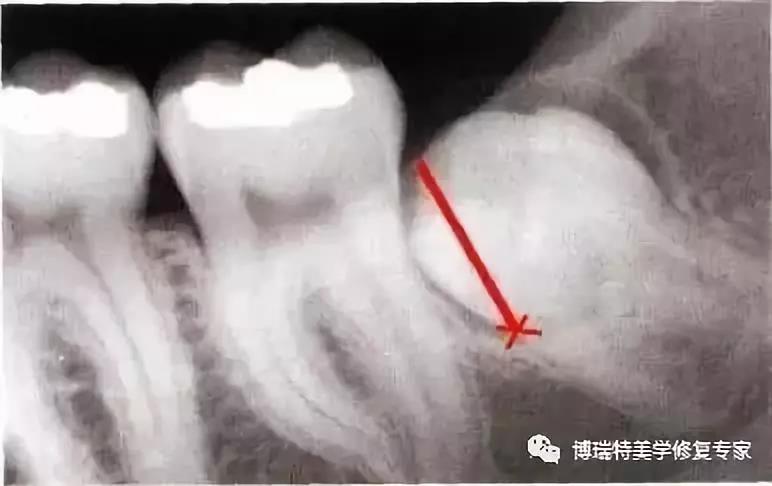

全颌曲面断层×线片,切割牙冠时应经过阻生牙远中面的牙颈部的釉牙骨质交界处。

下颌升支前缘的骨吸收区有利于牙片的取出。

去除颊侧部分骨阻力后,用装在反角机头上的纺锤形车针切割牙冠,用柔韧的小拉钩保护舌侧的黏骨膜。(及舌神经)

该病例也可以不切割牙冠而拔除。拔牙时,去除了牙根间隔。